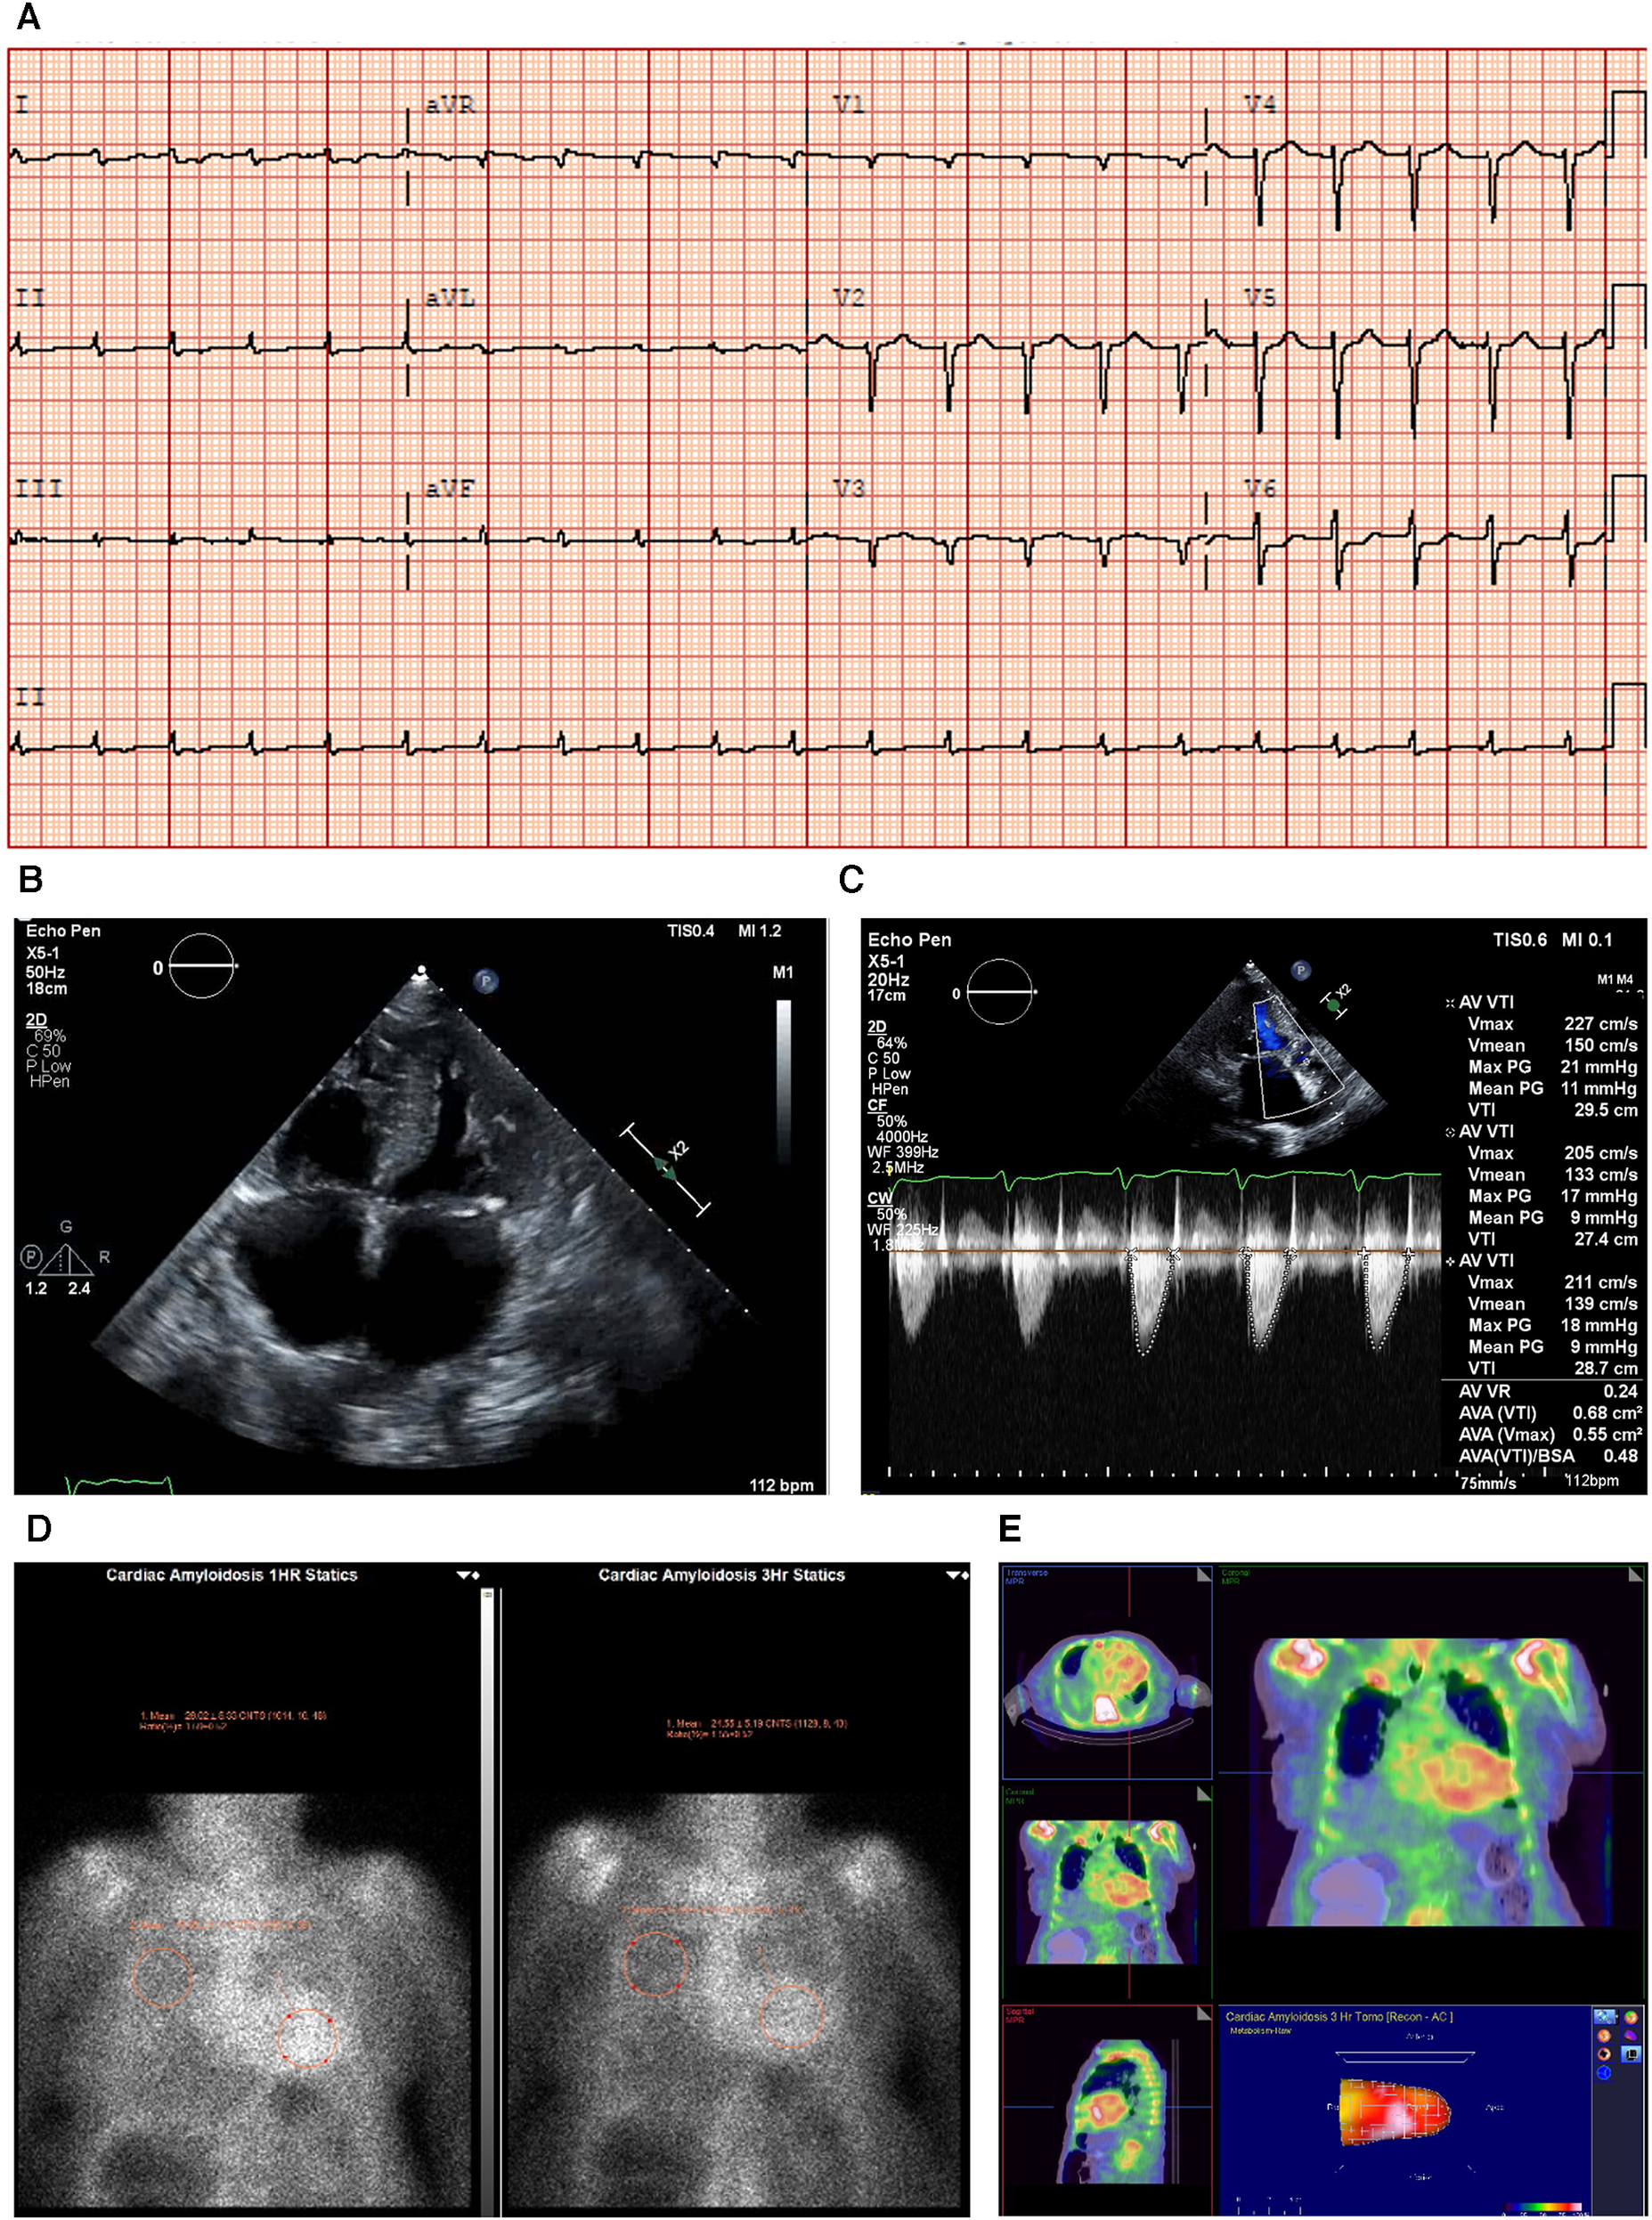

Figure 2

Case 2 clinical investigations. (A) An ECG showing sinus rhythm, low-voltage limb leads, poor R-wave progression, and a pseudo-infarct pattern. (B) A 2D echocardiography with a four-chamber view showing marked concentric LV hypertrophy and biatrial enlargement. (C) Continuous-wave Doppler of the AV is consistent with paradoxical low-flow/low-gradient. The calculated AV area index was 0.45 cm2/m. (D) Planar bone scintigraphy (99mTc-PYP) scan at 1 h and 3 h showing grade 3 myocardial uptake. (E) A SPECT scan demonstrating a strongly positive uptake (grade 3) with clear-cut differentiation between the LV cavity and myocardial uptake.

AV, aortic valve; ECG, electrocardiogram; LV, left ventricular; SPECT, Single-photon emission computed tomography; 99mTc-PYP, technetium pyrophosphate.

An echocardiography demonstrated a small left ventricle with severe concentric LV hypertrophy (R). LV systolic function was mildly decreased. The EF was estimated at 50 ± 5% with resting wall motion abnormalities. The right ventricle was normal in size, but RV systolic function was moderately to severely decreased [RV fractional area change, 22%; RVEF, 27%; tricuspid annular plane systolic excursion (TAPSE), 9 mm; RV basal diameter, 38 mm] (Figure 2B). The left and right atrial cavities were severely dilated. There was a severe AV stenosis caused by a calcified valve and a restricted opening. The overall findings were consistent with paradoxical low-flow/low-gradient severe AS. The SVi was 12 ml/m2, AV area index was 0.45 cm2/m, peak gradient was 17 mmHg, and mean gradient was 8 mmHg (Figure 2C). The E/A ratio could not be obtained as the patient had chronic AF.

Due to the strong clinical suspicion of CA, a 99mTc-PYP scan was conducted (Figure 2D). In semiquantitative assessment, myocardial PYP uptake was higher than rib uptake (grade 3). At 1 and 3 h SPECT studies, no evidence of excess blood pool was noted in the LV cavity (Figure 2E). At 1 h, the H/CL ratio was 1.61, and at 3 h, the H/CL ratio was 1.55.

Serum and urine immunofixation presented an apparent normal pattern, demonstrating that this patient had ATTR-CM. The troponin T level was 0.193 μg/L (reference range <0.06 μg/L) (I).